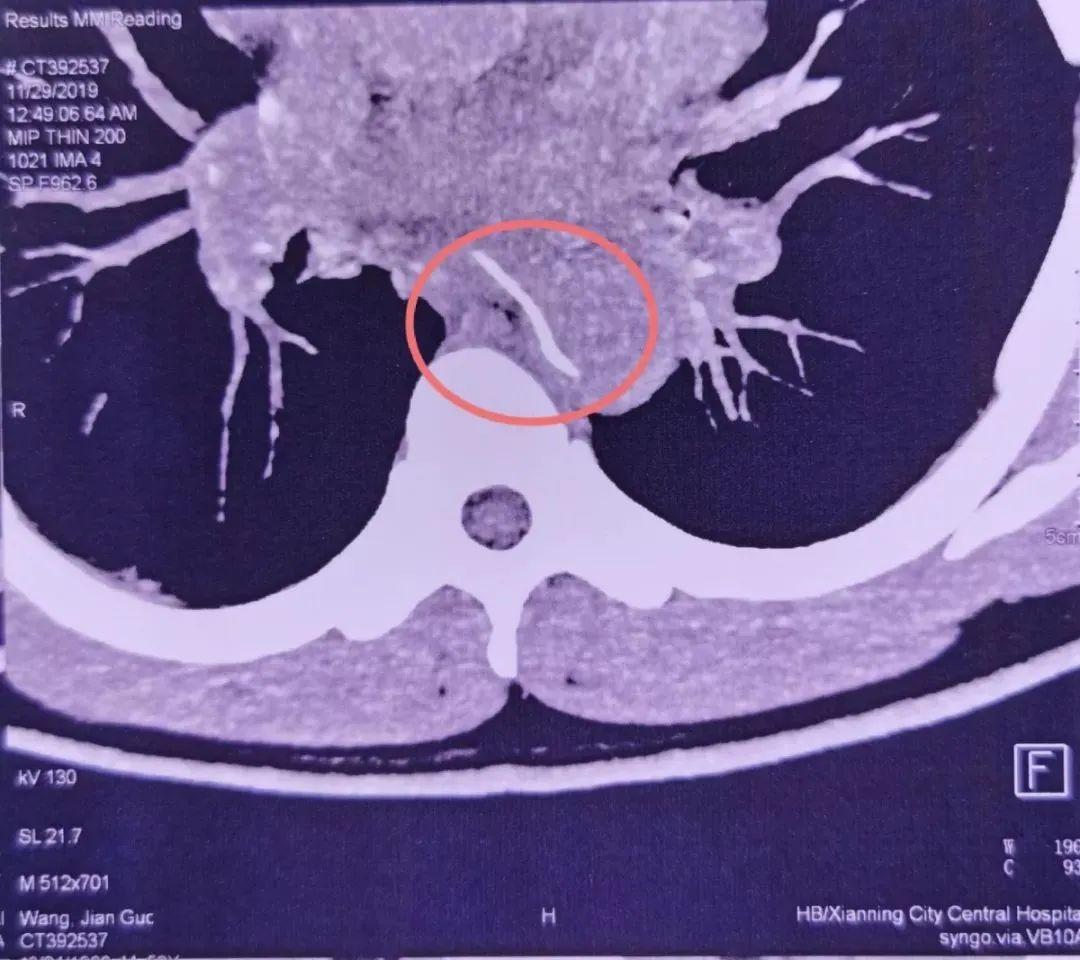

檢查過後,發現一根長達4cm的魚刺卡在他的食管上端,並且已經刺穿食管和胸主動脈,這正是他大量嘔血的原因。

胸主動脈,作為人體最粗大的動脈血管,血管壓力很高,如果形成破口,出血就會呈噴射狀。這個場景就好比「大壩決堤」,幾乎沒有搶救的機會。

就算醫生再見多識廣,也會覺得這很罕見,甚至一開始以為裡面的是塑料牙籤。畢竟這麼長、這麼尖的魚刺,人怎麼能吞得下去呢?